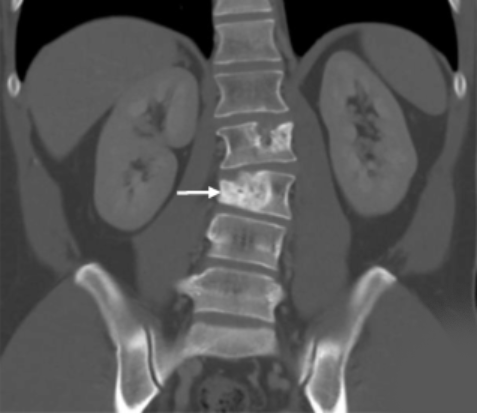

Seven patients chose this option and, so far, none have had evidence on imaging scans that their tumors are growing again.